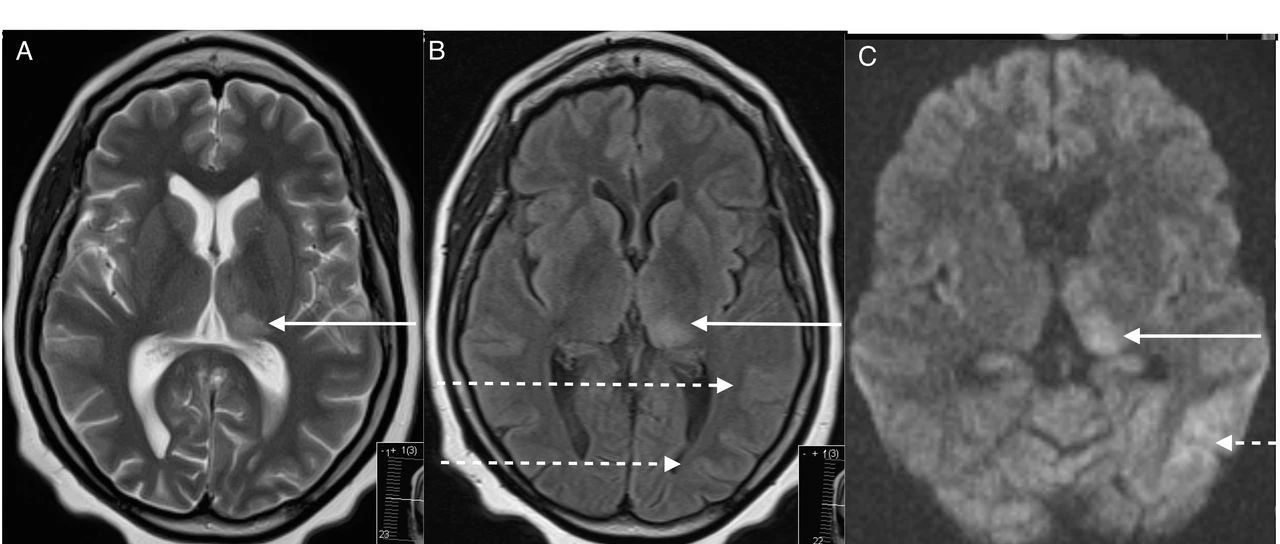

神经病学综合征:脑-眼-耳综合征(brain, eye, ear syndromes)

中枢神经系统症状,视觉障碍和听力缺损,此三联征是临床上经常遇到的情况。其中,免疫介导的疾病所占比例较大,如Susac综合征,Cogan综合征,Vogt-小柳原田综合征,脱髓鞘疾病(包括多发性硬化或视神经脊髓炎谱系疾病等),风湿免疫性疾病(包括系统性红斑狼疮,干燥综合征,白塞病和结节病等)。有学者提出了“脑-眼-耳综合征(brain, eye, ear syndromes,BEE syndromes)”这一新名词。...